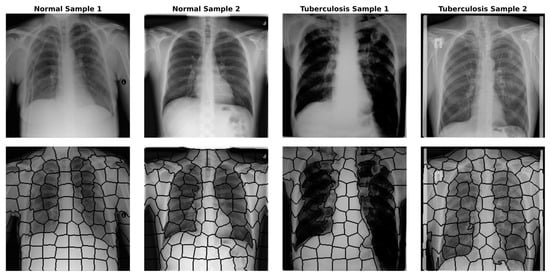

4.2. Image to Graph

- Colour and Intensity: Instead of the RGB space, we utilised the CIELAB colour space, which is perceptually uniform. We calculated the mean values of the L, A, and B channels for pixels within to represent average intensity and colour variations, which are crucial for identifying lesions under varying illumination conditions.

- Texture Descriptors: Since tuberculosis significantly alters lung tissue texture (e.g., infiltrations or consolidation), we extracted texture features to capture these irregularities. We computed Local Binary Patterns (LBP) histograms (radius = 3, points = 24) to encode micro-texture invariance. Additionally, Haralick features (Contrast, Correlation, Energy, and Homogeneity) were derived from the Grey-Level Co-occurrence Matrix (GLCM) to quantify structural dependencies at the regional level.

- Shape Invariants: To characterise the geometry of segmented regions independent of their orientation or scale, we calculated the seven invariant Hu Moments for each superpixel mask. This helps the model distinguish specific anatomical shapes regardless of patient positioning.

- Spatial Location: The normalised centroid coordinates (x,y) were included to allow the GNN to learn position-dependent priors, such as the likelihood of infection in specific lung lobes.